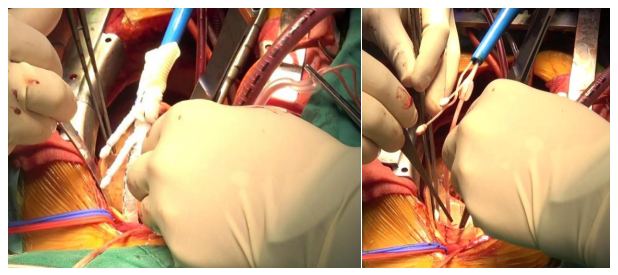

在麻醉手术中心的充分准备和支持下,手术如期实施。患者全麻,正中开胸并建立体外循环。体外循环开始转机并迅速降温。升主动脉远段阻断主动脉后灌入含血高钾心脏停跳液,心包内局部置入冰屑,心脏停跳。于窦管交界上方约1cm处横断升主动脉内膜,心包补片联合人工血管环加固主动脉根部。继续降温至24度全身停循环,经上腔静脉逆灌行脑灌注,打开显露主动脉弓部,选择PerMed 30-26-10-12-120双分支支架,支架主体置入降主动脉,双分支分别置入左锁骨下动脉及左颈总动脉,依次释放主体支架远端及左锁骨下动脉分支支架,随后根据患者弓部情况再次精准调节主体支架近端及左颈总动脉分支支架位置使之适应贴合主动脉弓,继而依次释放左颈总动脉分支支架和主体支架近端。连续吻合四分支人工血管与双分支支架近端,恢复全身循环,再连续吻合四分支人工血管近端于主动脉根部。开放主动脉后心脏自动复跳,最后吻合无名动脉,辅助循环直至停机撤除体外循环,安置心包纵隔引流管逐层关胸,手术顺利结束,患者送往监护室。